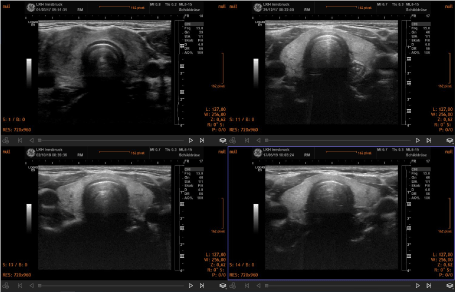

Over a period of 18-24 months, signs of improved morphology and decreased vascularization were seen. In general, the morphological changes included a reduction of thyroid volume and a normalization of the structure of the gland in cases of subacute thyroiditis. Two representative clinical cases are shown in the figure 1. In hyperthyroidism the pattern of increased vascularization of the gland normalized during treatment (Figure 2). Thyroid morphology also showed improvement (Figure 3).

Figure 3. Sequential demonstration of partial normalization of thyroid morphology in a case of Grave’s disease